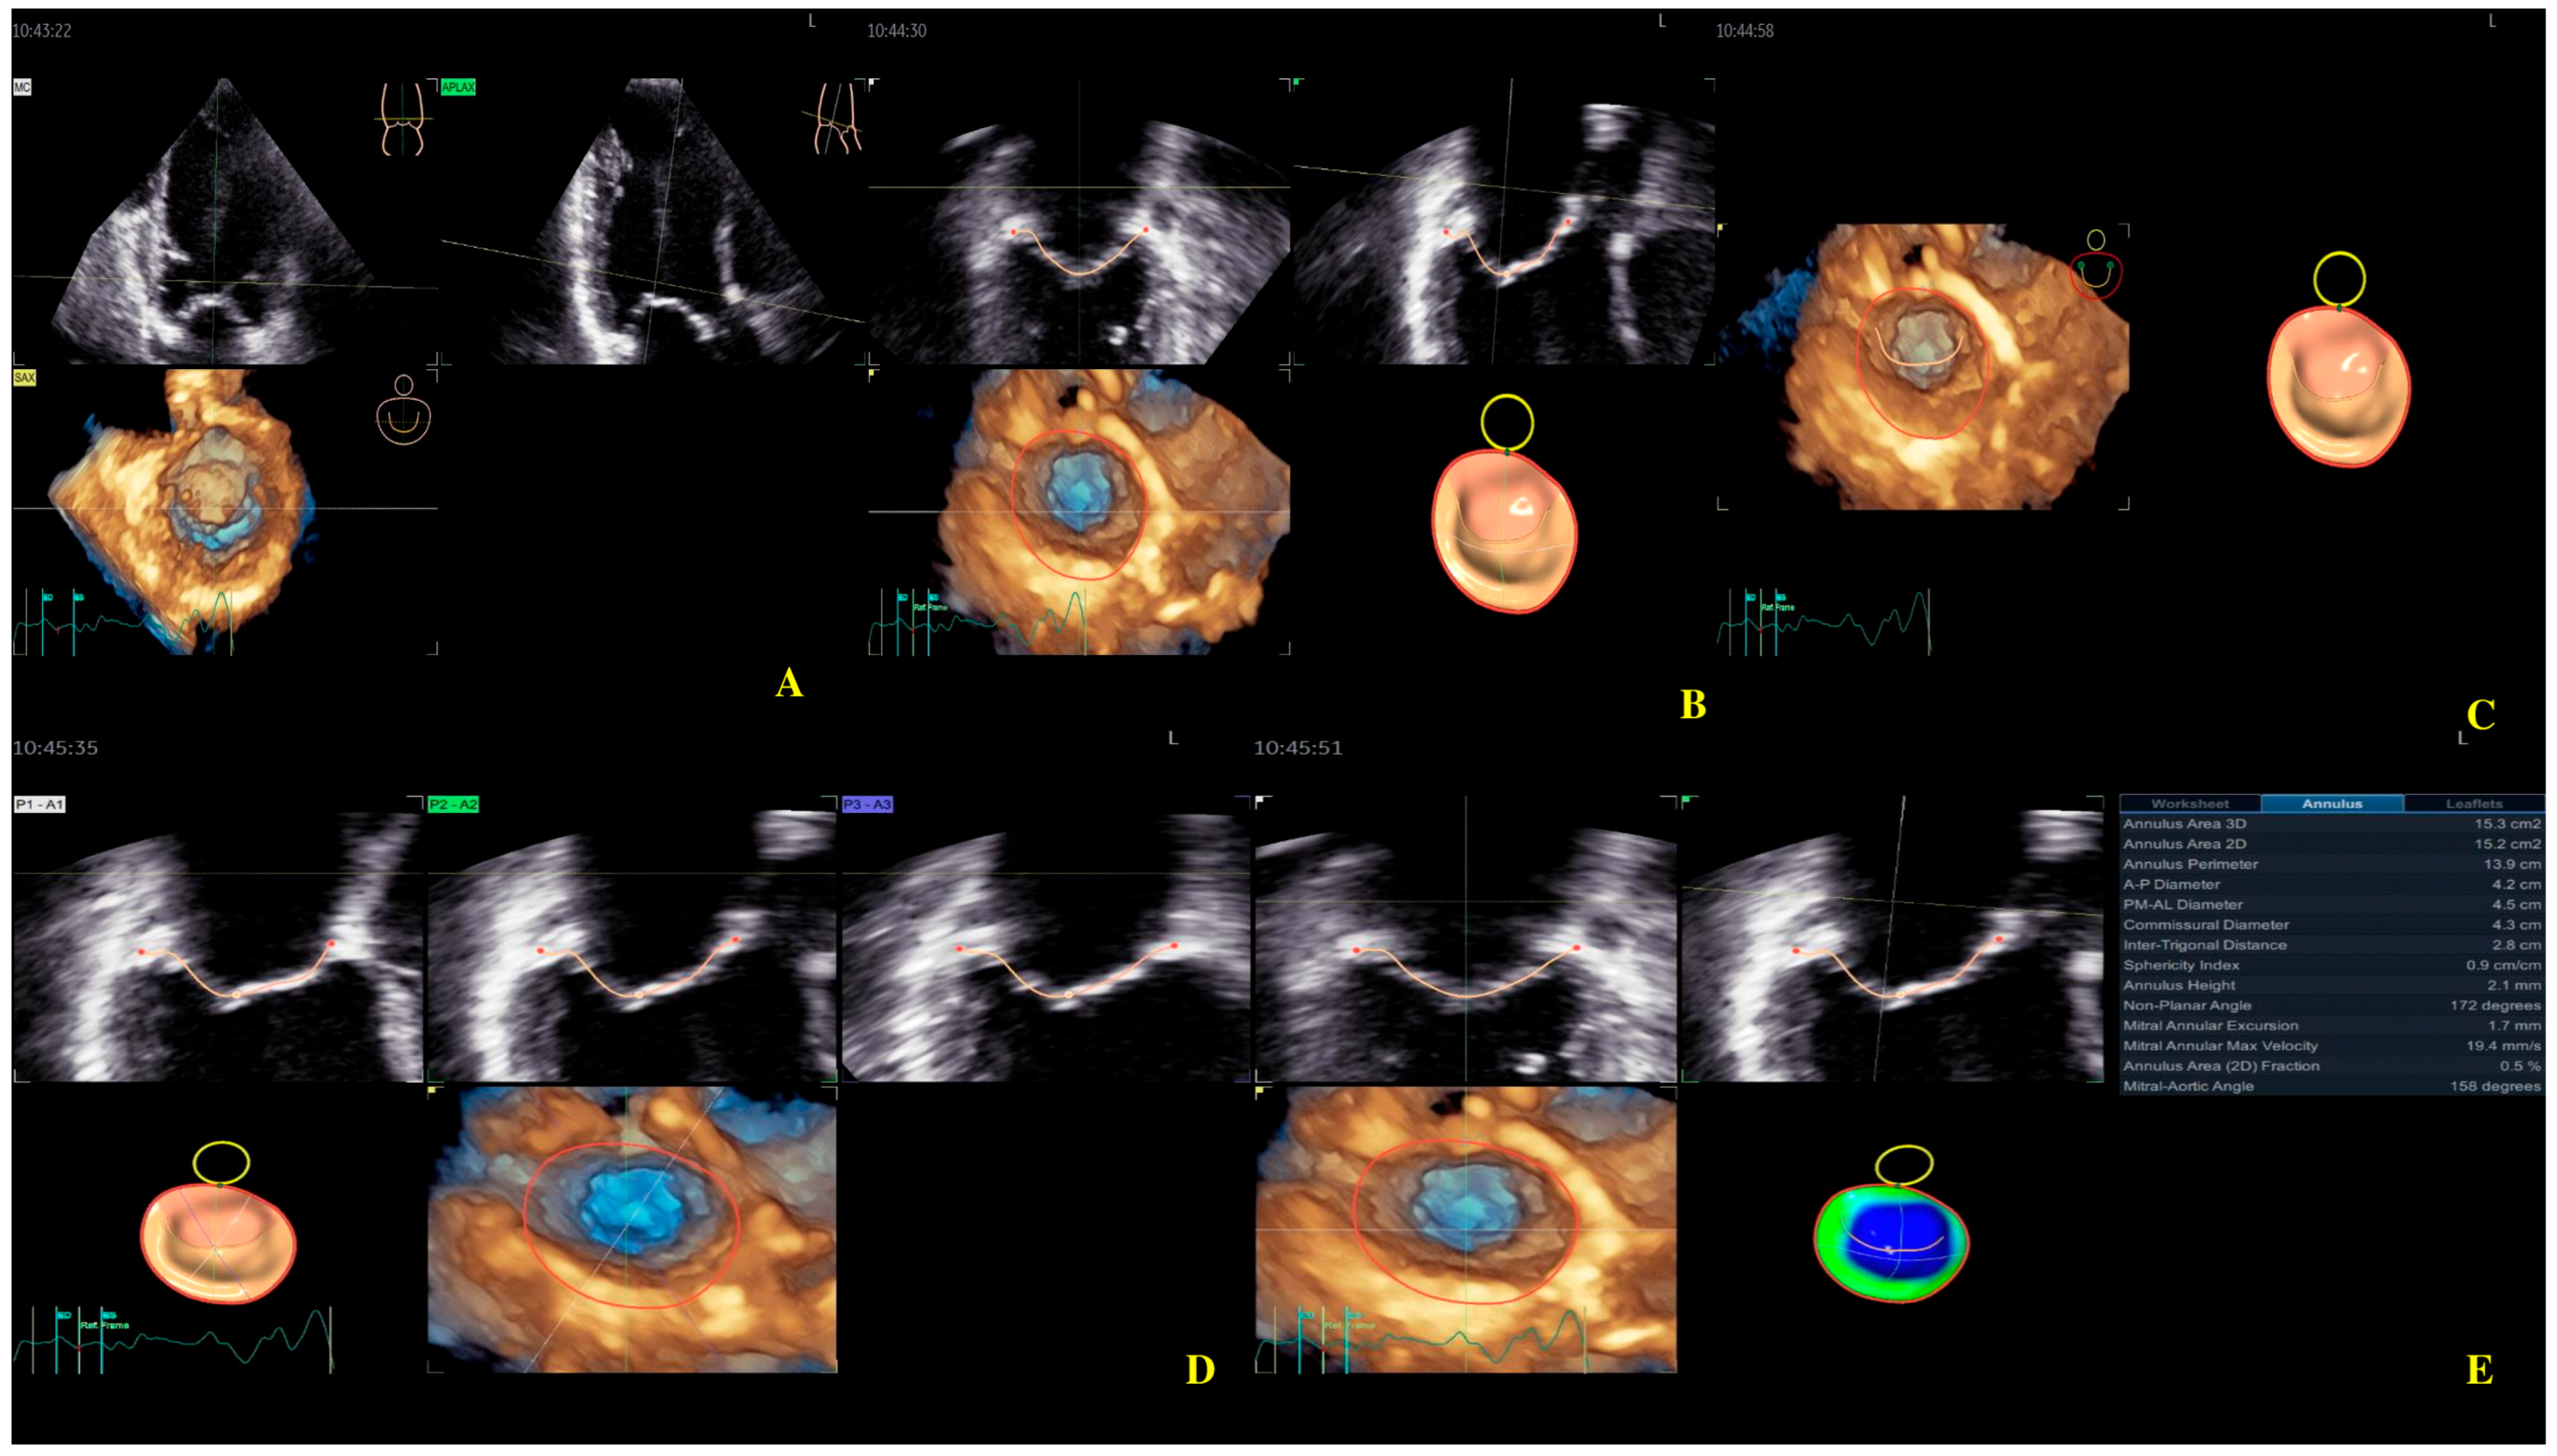

Four-dimensional echocardiography image acquisition of the MV for quantitative analysis is usually performed in the A4ch view on transthoracic echocardiography [23,24]. An optimal view was selected for the most MV favorable segmentation. The 4D Auto MVQ software package enabled the detection of anatomic landmarks (Figure 4), followed by surface modeling using a geometric mesh. Finally, we obtained the annular and leaflet geometry, as well as their dynamics (Figure 5) [25,26,27].

Figure 4.

Mitral valve segmentation and quantification (A), detection of mitral valve anatomic landmarks (B), mitral valve commissures pointing (C), mitral valve scallops pointing (D), mitral annulus parameters (E).